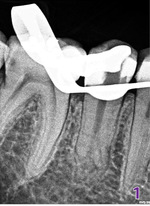

Do gabinetu stomatologicznego zgłosiła się pacjentka z powodu silnych dolegliwości bólowych zęba 45. Na podstawie zebranego wywiadu i badania podjęto decyzję o natychmiastowym leczeniu endodontycznym z powodu nieodwracalnego zapalenia miazgi. Wykonane zostało zdjęcie RVG, na którym odnotowano nietypową anatomię korzeni (fot. 1), co umożliwiło wyznaczenie kierunku dalszej procedury zabiegu.